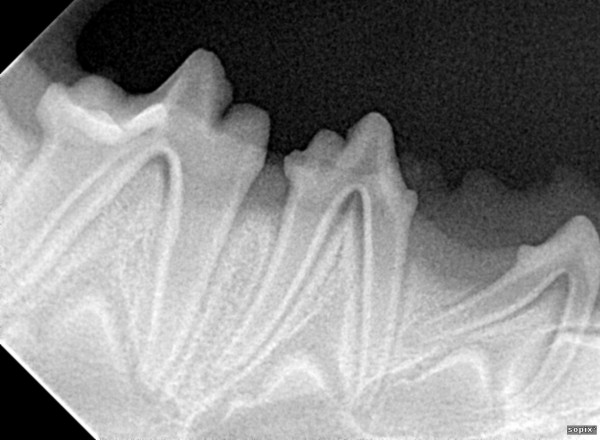

Radiographie dentaire.

Nous sommes équipés d’un système de radiographie dentaire spécifique, indispensable pour :

- évaluer l’état des racines dentaires,

- préparer et contrôler les extractions dentaires, en s’assurant de l’absence de fragments résiduels qui pourraient entretenir douleur et inflammation, notamment lors de gingivostomatites du chat,

- réaliser le dépistage précoce de l’agénésie dentaire chez le chiot, outil essentiel pour la sélection et la reproduction.